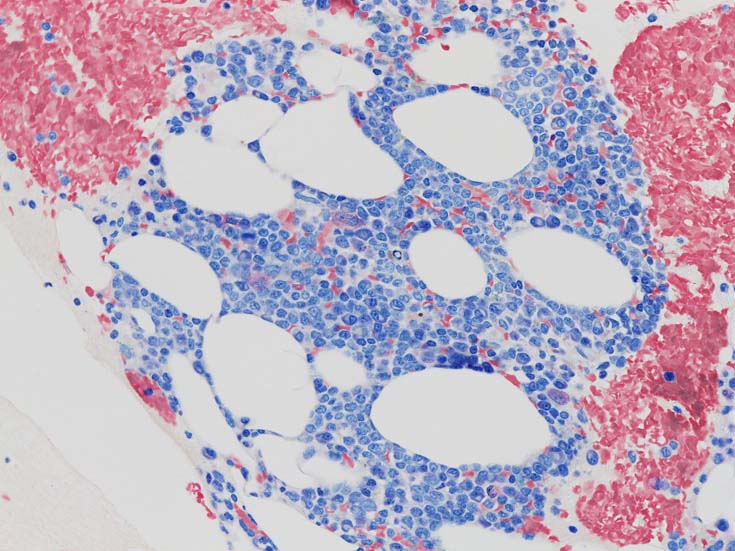

cellularityは60-70%. 赤芽球血島形成はみられない. Naphtol-ASD-CAE染色に赤染される顆粒球系細胞もごくわずか. 成熟Mgkもごく少数で, 正常造血は強く抑制されている.

類円形あるいは, シワのみられるconvolutedな核に核小体をもつN/C比大の細胞が増加している. クロマチンは微細で核は淡明にみえる.Naphtol-ASD-CAE染色陰性.幼若あるいは活性化されたリンパ球様細胞に似ている.

形質細胞の凝集増加がめだつ.